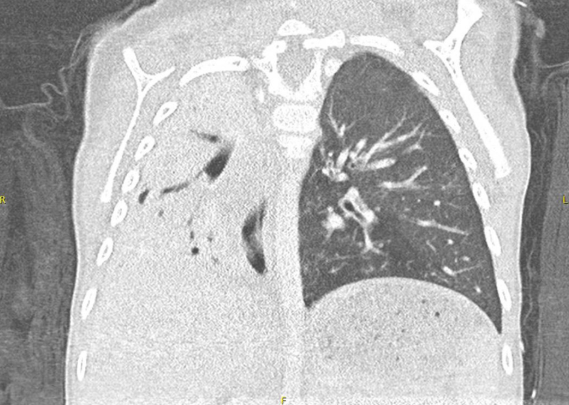

Further imaging, including a chest CT scan, confirmed the diagnosis of Swyer-James-Macleod Syndrome. The CT revealed unilateral hyperlucency of the left lung, extensive opacification of the right hemithorax, and atelectasis of the right upper and middle lobes with superimposed bronchiectasis.

SJMS is a post-infectious condition, typically following a viral or bacterial infection in early childhood. It leads to bronchial narrowing, reduced airflow, and decreased blood flow to parts of the lung, resulting in characteristic imaging findings.